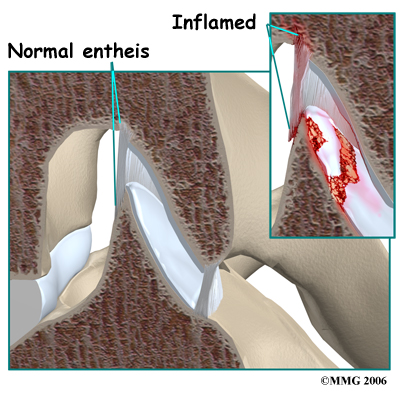

In some rheumatological diseases, the inflammatory process affects other areas of connective tissue such as where ligaments and tendons attach to the bone. This area is called an enthesis. There are entheses located all over the body with many in the spine itself, such as where the intervertebral disc attaches to the vertebra. Many of the rheumatological diseases that affect the spine seem to attack these particular areas of the spine but it is unclear why this occurs.

In some rheumatological diseases, the inflammatory process affects other areas of connective tissue such as where ligaments and tendons attach to the bone. This area is called an enthesis. There are entheses located all over the body with many in the spine itself, such as where the intervertebral disc attaches to the vertebra. Many of the rheumatological diseases that affect the spine seem to attack these particular areas of the spine but it is unclear why this occurs.

In some rheumatological diseases, the inflammatory process affects other areas of connective tissue such as where ligaments and tendons attach to the bone. This area is called an enthesis. There are entheses located all over the body with many in the spine itself, such as where the intervertebral disc attaches to the vertebra. Many of the rheumatological diseases that affect the spine seem to attack these particular areas of the spine but it is unclear why this occurs.

In some rheumatological diseases, the inflammatory process affects other areas of connective tissue such as where ligaments and tendons attach to the bone. This area is called an enthesis. There are entheses located all over the body with many in the spine itself, such as where the intervertebral disc attaches to the vertebra. Many of the rheumatological diseases that affect the spine seem to attack these particular areas of the spine but it is unclear why this occurs.